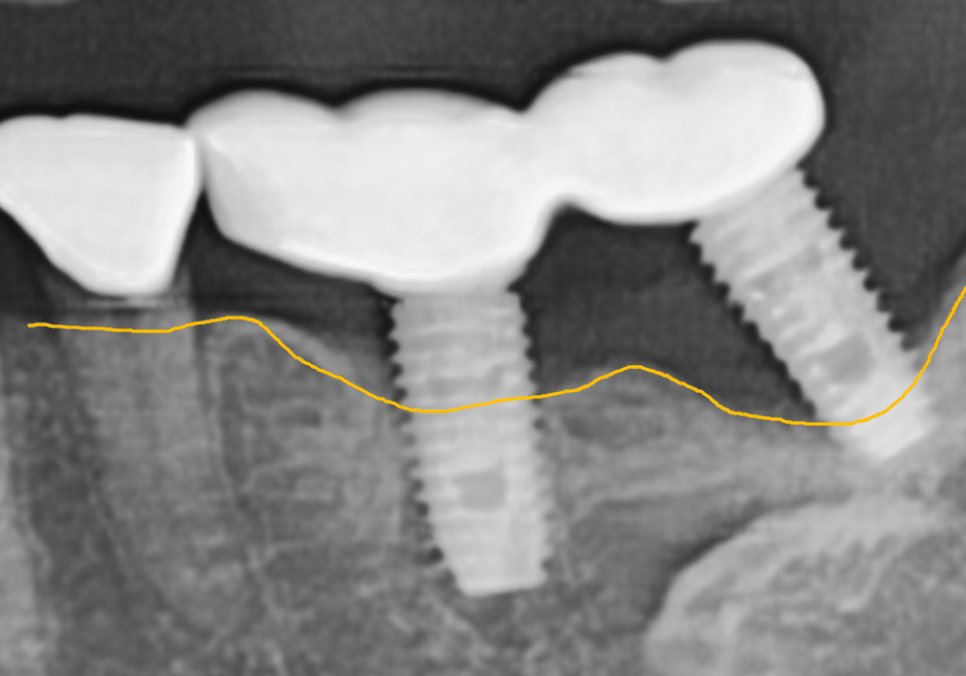

방사선 사진을 보니 상태가

더 명확했는데요.

바로 옆 임플란트(#36)는

뼈가 꽉 차 있는 반면,

맨 끝 임플란트(#37)는

뿌리 주변의 뼈가 까맣게 녹아내려

텅 비어 있는 상태였습니다.